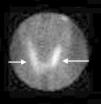

Tras 3 meses de evolución, comienza con temblores, sudoración, palpitaciones y picos febriles. Estos síntomas se controlaron con propranolol, y para realizar el diagnóstico diferencial con la enfermedad de Graves solicitamos una nueva analítica y gammagrafía tiroidea con radioyodo. Los anticuerpos antitiroglobulina, antiperoxidasa tiroidea y estimulantes de tiroides (TSI) resultaron negativos, y las hormonas tiroideas permanecían en el mismo valor. Finalmente, la gammagrafía tiroidea mostró ausencia de captación (fig. 1), lo que determinó el diagnóstico de tiroiditis subaguda. Una vez que se limitó el dolor, se sucedió una fase de hipotiroidismo asintomático antes de la normalización analítica en 6 meses.

El diagnóstico de confirmación se obtiene al observar una reducción de la captación de radioyodo en la gammagrafía (1-3%) durante la fase de hipertiroidismo. En pacientes con una clínica típica, esta prueba puede ser omitida y monitorizarse la función tiroidea. Si el dolor se resuelve y la función se normaliza en varias semanas, el diagnóstico de tiroiditis subaguda estará hecho4. Para pacientes en los que la presentación clínica sea atípica se puede emplear una ecografía para diferenciarlo de otras enfermedades5.

En esta paciente, dado que la fase hipertiroidea era prolongada y se iniciaron tardíamente los síntomas de hipertiroidismo, decidimos realizar el diagnóstico diferencial con la enfermedad de Graves, que también puede asociar dolor7 o incluso comienza tras una tiroiditis subaguda8. El motivo del dolor no ha sido aclarado, y su inicio tras una tiroiditis se debe a la generación de una respuesta inmune tras la destrucción de la glándula tiroidea por la inflamación. La negatividad de las determinaciones inmunológicas y la ausencia de captación tiroidea en la gammagrafía nos ayudó a realizar el diagnóstico diferencial entre el hipertiroidismo de la tiroiditis subaguda y de la enfermedad de Graves.